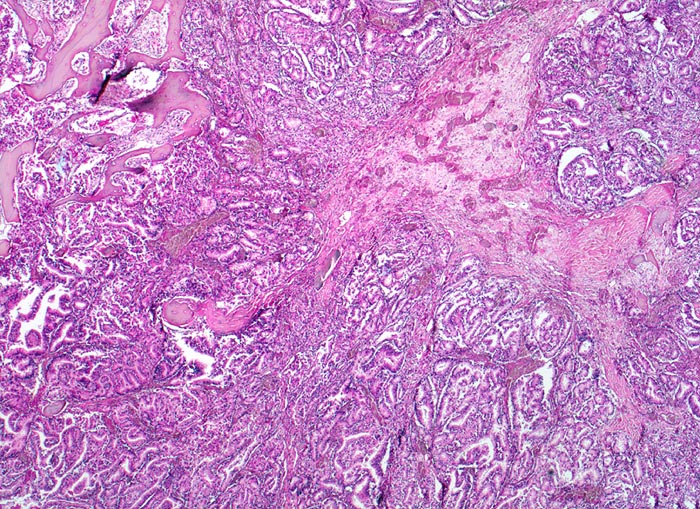

Da Adenokarzinome neben der Prostata in fast allen Organen vorkommenen, ist die Differentialdiagnose im HE Schnitt bei Nachweis einer Knochenmetastase eines Adenokarzinoms sehr breit. Die immunhistochemische Positivität der Tumorzellen für prostataspezifisches Antigen (PSA) spricht für eine Primärtumorherkunft aus der Prostata. Prostatakarzinome bilden typischerweise osteoplastische Knochenmetastasen. Die Knochenbildung erfolgt via Cytokine und Wachstumsfaktoren, die von den Tumorzellen gebildet werden (z.B. TGF-beta), durch Stimulation der Osteoblasten, wahrscheinlich bei gleichzeitiger lokaler Reduktion der Osteoklastenaktivität (RANK/RANKL/OPG-System). Die Stimulation von Osteoblasten führt zu einer vermehrten appositionellen Osteoidneubildung entlang vorhandener Trabekel mit nachfolgender Mineralisierung. Durch fortgeschrittene Knochenneubildung kommt es zu einer vollständigen Ummauerung grösserer Tumorareale, welche durch die verminderte Blutzufuhr nekrotisch werden. Vielfach lassen sich histologisch osteoplastische und osteolytische Anteile nachweisen. Immunhistochemisch lässt sich in den Metastasen oft Prostata spezifisches Antigen nachweisen (> 5342).

Morphologische Merkmale:

• Fehlen von blutbildendem Knochenmark.

• Infiltration des Knochemarks durch kleine dichtgepackte, kribriforme Strukturen ausbildende Karzinomdrüsen.

• Osteplastische Metastase: Faserknochenneubildung zwischen vorbestehenden Trabekeln.

• Anhand der Histologie kann lediglich die Diagnose einer Metastase eines Adenokarzinoms gestellt werden. Kleine, solide Verbände bildende Tumordrüsen und grosse Nukleolen sind typisch für ein Prostatakarzinom. Die Diagnose muss aber durch den Vergleich mit der Morphologie des Primärtumors oder eine Immunhistochemische Untersuchung (PSA, PSAP) bestätigt werden.